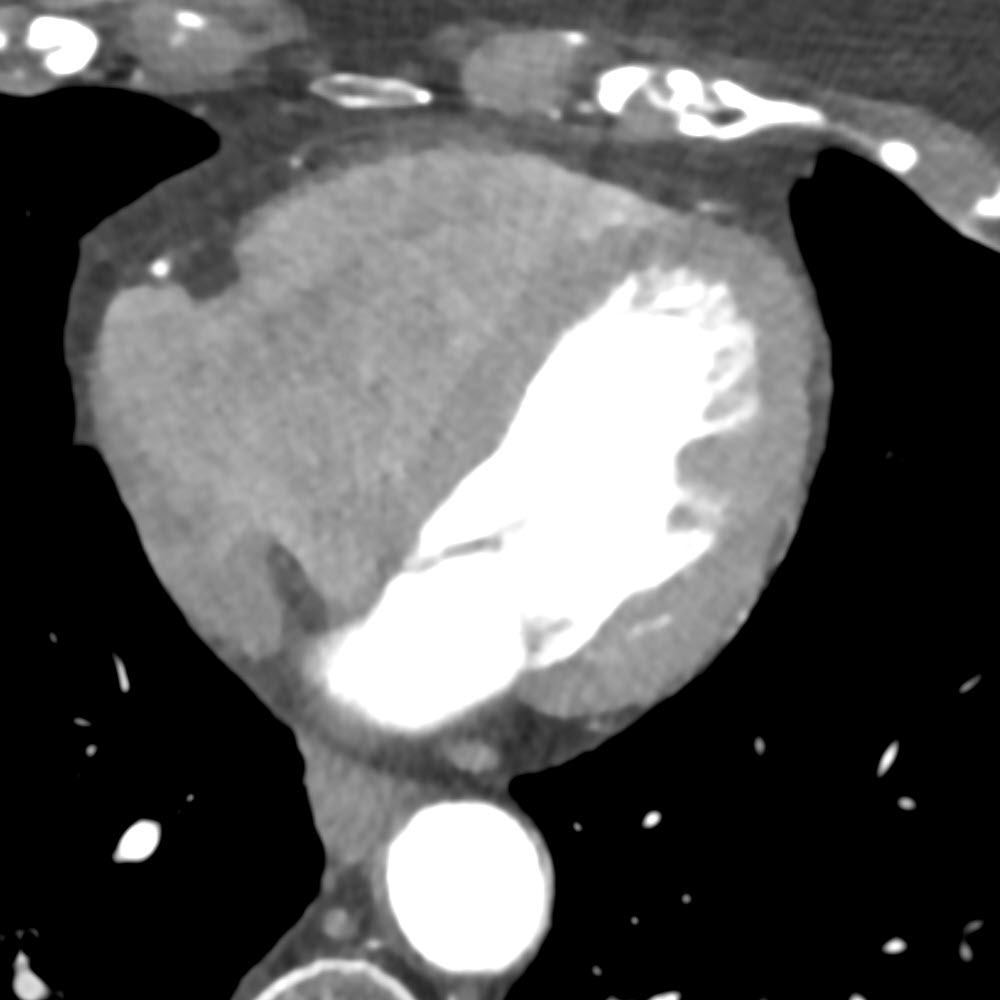

Fusion von PET und CT

Schicht-Rekonstruktion des Herzens mit Darstellung einer Kontrastmittel-gestützten CT-Untersuchung (links) sowie überlagert die Informationen zur Durchblutung des Herzmuskels (rechts, PET).